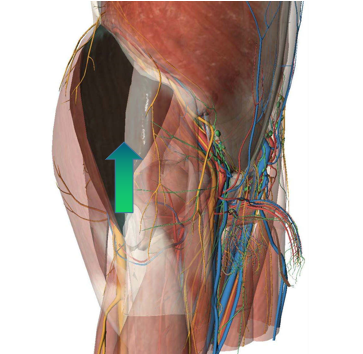

圖七

針對(duì)周先生的情況,李寬新主任、張衡博士在手術(shù)前進(jìn)行了詳細(xì)完備的術(shù)前設(shè)計(jì)(圖四),并在3Dbody、Mimics、Magic軟件上進(jìn)行入路設(shè)計(jì)和模擬手術(shù)(圖五、六),計(jì)算出髖臼杯和股骨柄大小及髖臼杯外展角、前傾角、旋轉(zhuǎn)中心位置等關(guān)鍵指標(biāo)。6月16日在周建生教授的指導(dǎo)支持下,由李寬新主任、張衡博士在我院成功應(yīng)用微創(chuàng)OCM入路聯(lián)合Harris窩技術(shù)為患者實(shí)施一期雙側(cè)人工全髖關(guān)節(jié)置換術(shù)。手術(shù)切口僅7cm,術(shù)中出血量約80ml。(圖七)

微創(chuàng)髖關(guān)節(jié)前外側(cè)入路最先由德國(guó) OCM(Orthopadische Chirurgie Munchen)醫(yī)院 Rottinge 和 Huhe 兩位醫(yī)生于2005年報(bào)道,故稱(chēng) OCM入路。此入路與傳統(tǒng)的后外側(cè)入路相比,優(yōu)勢(shì)在于選擇了臀中肌和闊筋膜張肌之間的肌間隙進(jìn)入,不會(huì)損傷髖關(guān)節(jié)外旋、外展肌群,可完整地保留髖關(guān)節(jié)囊,不會(huì)干擾髖關(guān)節(jié)后外側(cè)解剖和生物力學(xué)結(jié)構(gòu),避免了術(shù)后髖關(guān)節(jié)后脫位等并發(fā)癥,切口小,出血少,術(shù)后功能恢復(fù)快,術(shù)后患者手術(shù)側(cè)的肢體無(wú)功能鍛煉禁忌動(dòng)作,因而具有圍手術(shù)期快速康復(fù)的優(yōu)勢(shì)。